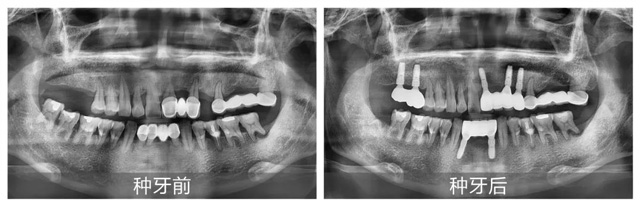

因牙周病的困扰,卞先生仅30多岁牙齿便接连松动脱落。2012年曾在伊犁某口腔机构进行烤瓷固定桥修复,但受限于当地医疗条件,且随着时间推移,上下颌前侧的多处修复体逐渐松动,加上上颌1颗前牙和右侧2颗磨牙的脱落,导致卞先生的咀嚼功能严重受损。

经CBCT全景检查所见,谢海洋主任发现卞先生存在多颗牙缺失、残存牙体伴有严重骨吸收,且多颗修复体失效等问题,亟待通过种植牙重建咬合功能。针对顾客异地就医、就诊时间有限的情况,谢海洋主任为卞先生制定了“上下颌多颗即拔即种+连冠修复”的个性化种植方案:下颌种植2颗基牙支撑2颗连冠,上颌右侧种植2颗独立基牙,上颌前侧种植3颗基牙连冠修复1颗。